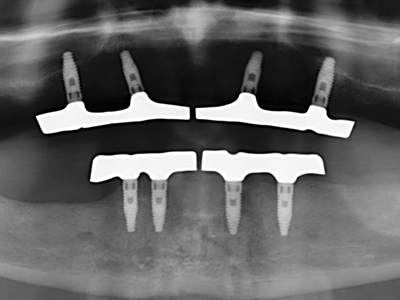

Fig. 11: The postoperative panoramic image shows the vertical augmentation and sinus floor elevation.

Fig. 15: The one-year follow-up x-ray examination shows stable conditions at the bone level.